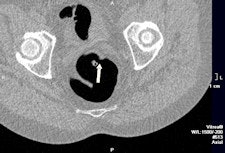

In a study published online March 11 by the European Journal of Radiology, five radiographers underwent a teletraining program on CTC based on interpretation of 75 cases. The group had no experience with CTC and only very basic knowledge of colonic anatomy and pathology, although they had practical experience of abdominal CT and barium enema procedures (EJR, March 11, 2011).

After initial training, good sensitivity and positive predictive value (PPV) were obtained for polyps with a diameter of more than 6 mm, according to lead author Carsten Lauridsen, from the department of radiography education at Copenhagen's Metropolitan University College. In the training cases, overall per-polyp sensitivity was between 57% and 69.1%. Overall per-patient sensitivity, specificity, and PPV sensitivity was between 78.3% and 86.4%. In the test cases, overall per-polyp sensitivity was between 80.7% and 94.7%, and overall per-patient sensitivity, specificity, and PPV were between 64% and 92.9%.